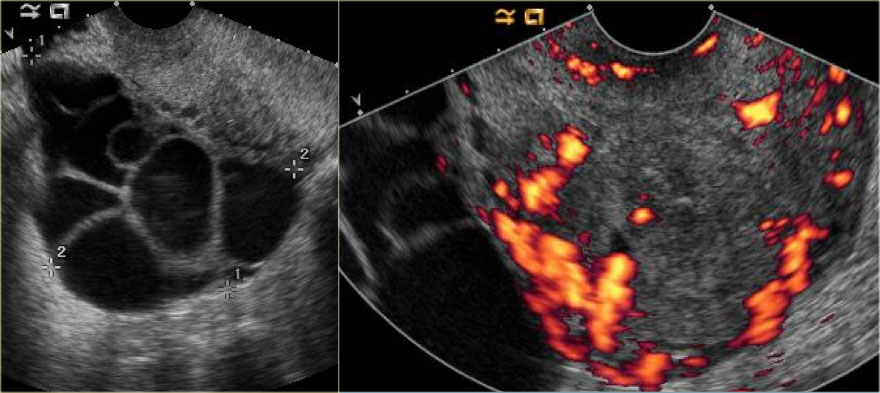

Прежде чем рассматривать патологические изменения, обсудим нормальную анатомию яичника. У женщины при рождении яичник содержит более двух миллионов первичных ооцитов. В каждом менструальном цикле созревает около десяти из них. Из зрелых Граафовых фолликулов только один становится доминирующим и достигает размера 18–20 мм к середине цикла, после чего разрывается, освобождая ооцит. Остальные фолликулы уменьшаются и замещаются фиброзной тканью. После выхода ооцита доминантный фолликул спадается, в его внутренней выстилке начинается разрастание грануляционной ткани с отеком, что приводит к образованию желтого тела менструации. Через 14 дней желтое тело претерпевает дегенеративные изменения, и на его месте остается мелкий рубец — белое тело.

Граафовы фолликулы — это небольшие кистозные образования, которые присутствуют в яичниках всех женщин репродуктивного возраста (в предменопаузальном периоде). Их размеры варьируют в зависимости от дня менструального цикла: доминирующий фолликул обычно не превышает 20 мм в диаметре к моменту овуляции (14-й день от начала менструации), остальные — не более 10 мм.

На УЗИ яичников визуализируются несколько анэхогенных простых кист (Граафовых фолликулов). Их не следует путать с патологическими кистами.